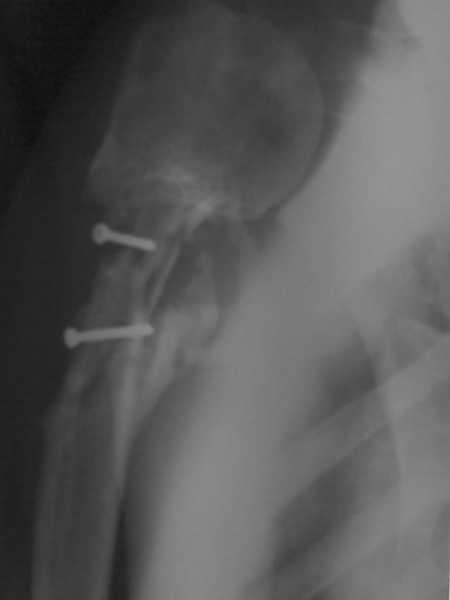

Более года назад пациент был оперирован в одном из НИИТО. При контрольном осмотре через год: болевой синдром, контрактура в локтевом суставе, патолгическая подвижность нижней трети плеча

Неудачный остеосинтез пластиной: поломка винтов, миграция фиксатора. После удаления пластины сформировался гипопластический ложный сустав нижней трети бедренной кости, укорочение н/к 5 см. Выполнялся дистакционный остеосинтез аппратом Илизарова на штифте. Зона ложного сустава "не открывалась". Через 10 месяцев, когда даже регенерат полностью перестроился, консолидации в зоне ложного сустава не наступило, несмотря на стабильную фиксацию и постоянную компрессию(штифт+аппрата на 4 кольцах).

Неудачный остеосинтез пластиной: поломка винтов. После удаления сформирался гиполастический ложный сустав. Остеосинтез АВФ, циклическая компрессия-дистракция в области ложного сустава привела к формированию хорошей рентгенологической костной мозоли. Через 1,5 месяца ходил в аппарате без дополнительных средств опоры. Через 6 месяцев после клинической пробы - демотаж. Через 4 месяца после демонтажа - лизис костной мозоли, рецидив деформации.